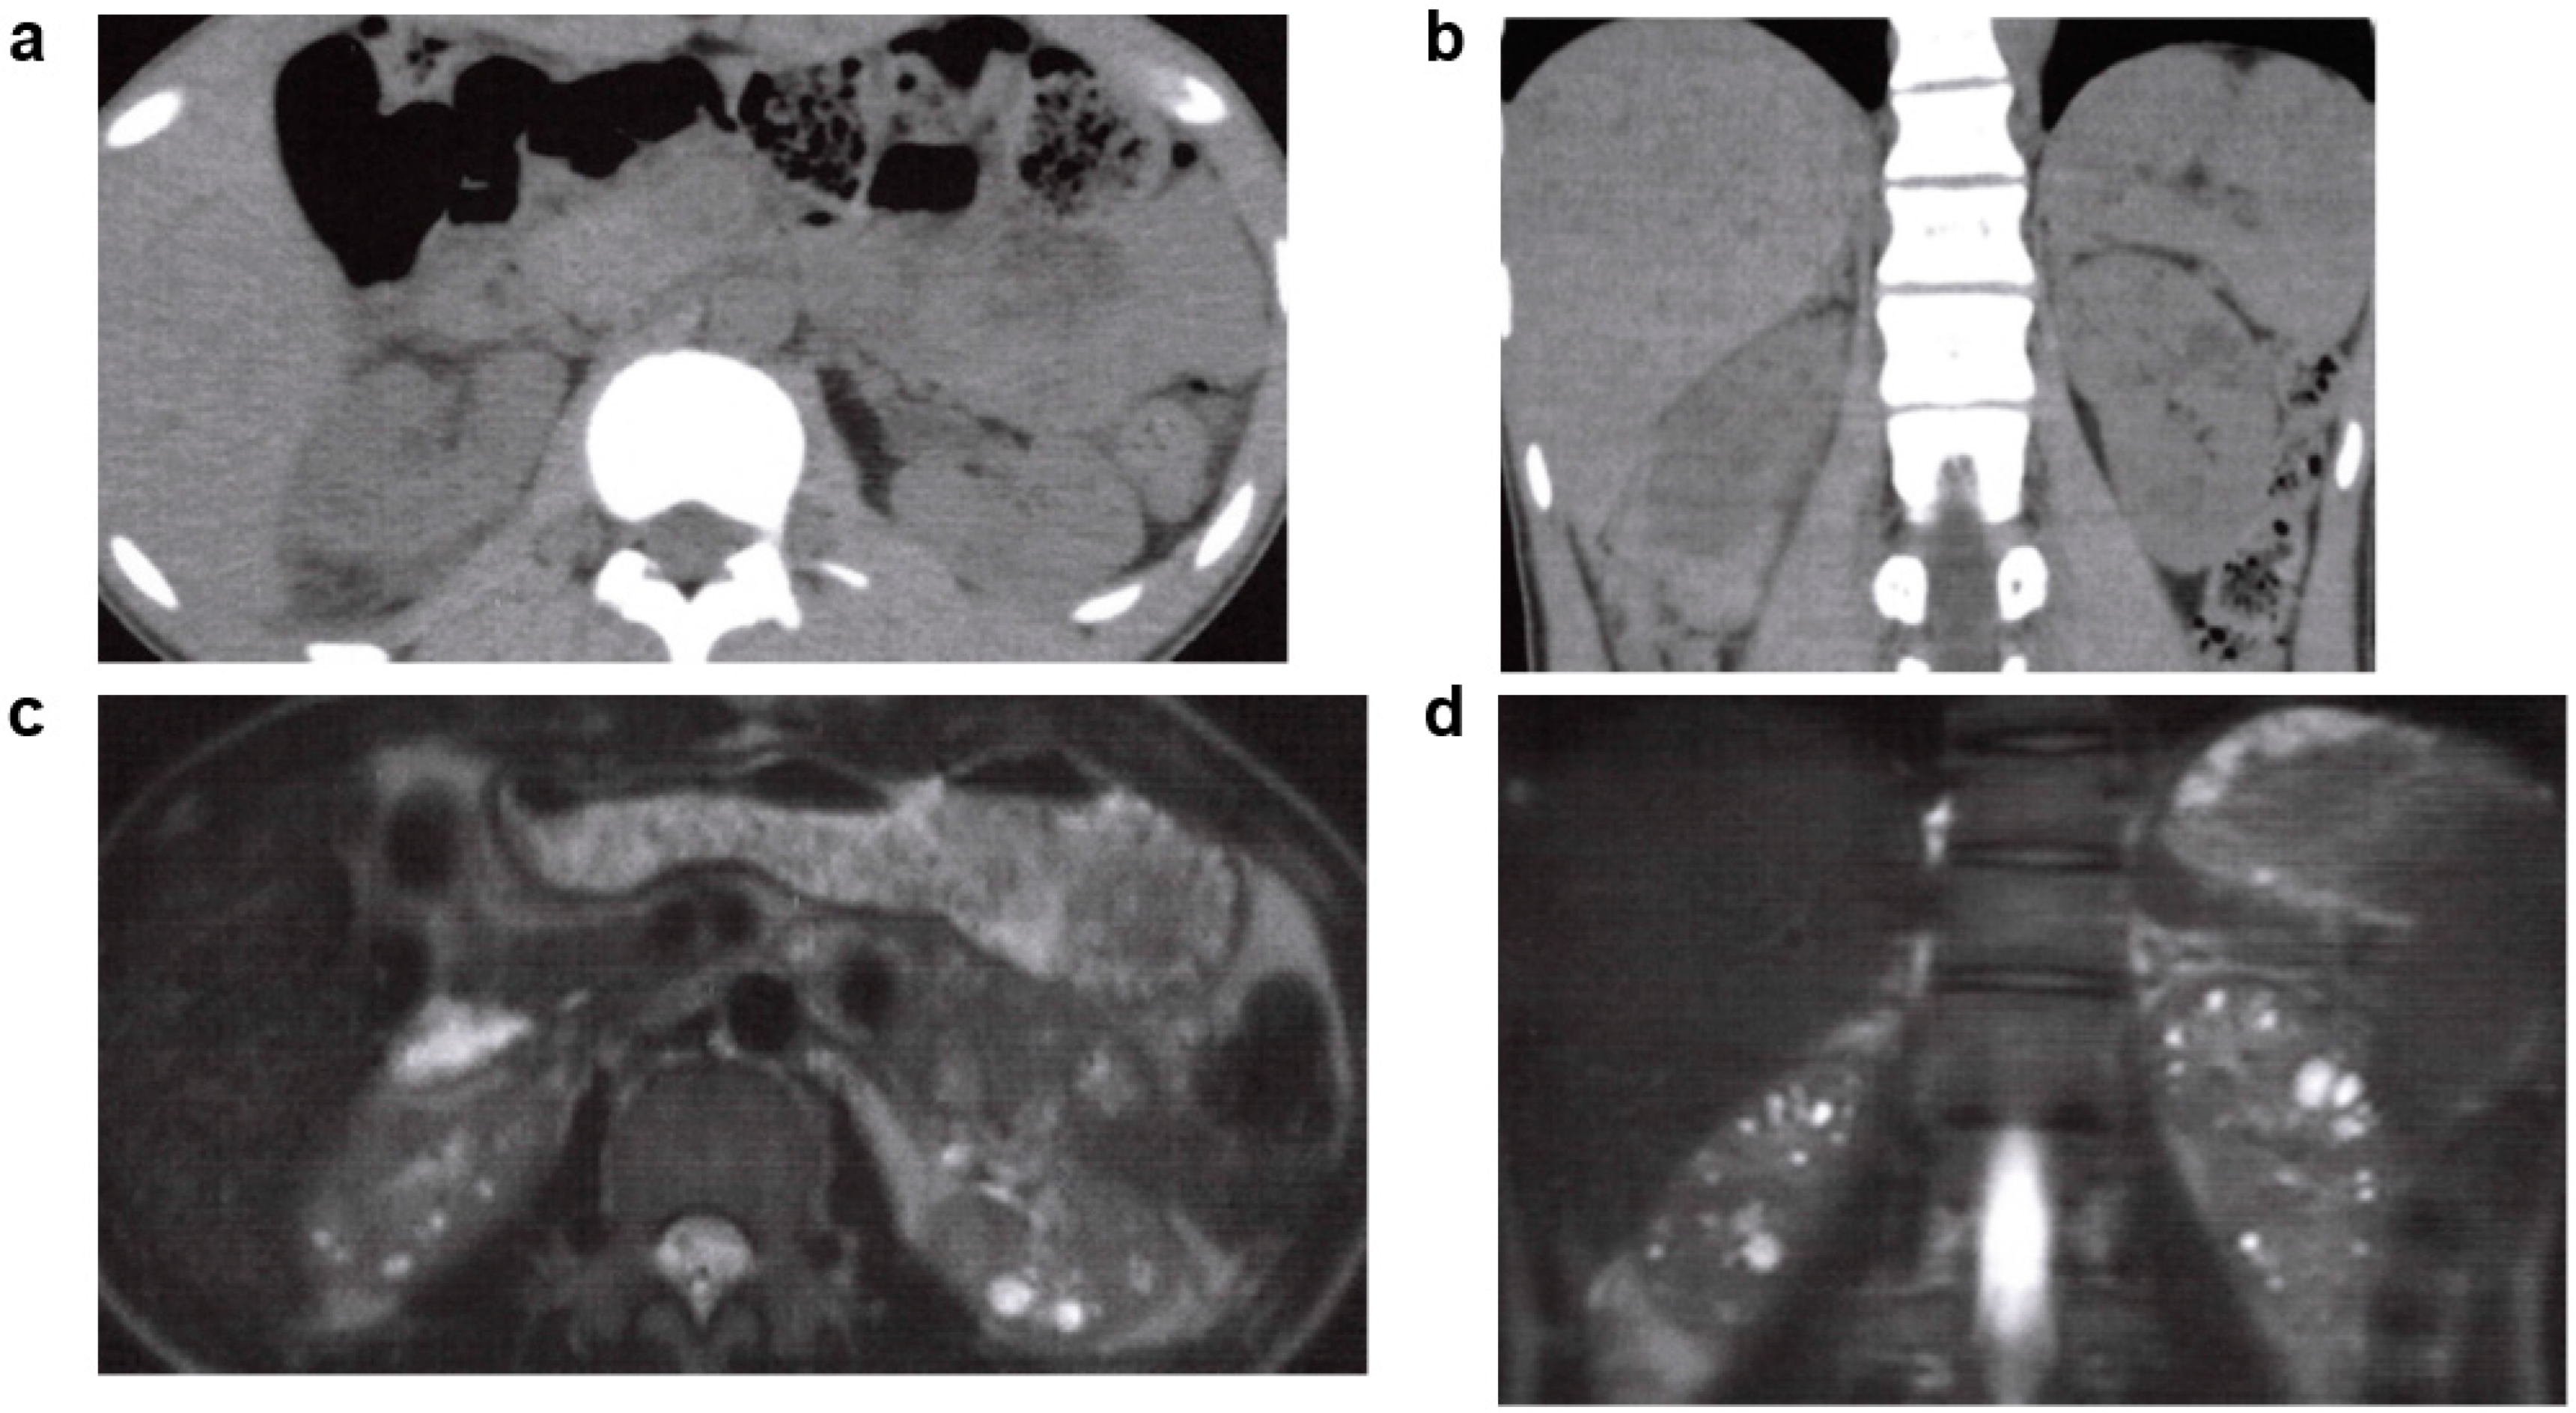

3.3. Nephronophthisis (NPH)

- Luo, F.; Tao, Y.H. Nephronophthisis: A review of genotype-phenotype correlation. Nephrology 2018, 23, 904–911. [Google Scholar] [CrossRef]

- Snoek, R.; van Setten, J.; Keating, B.J.; Israni, A.K.; Jacobson, P.A.; Oetting, W.S.; Matas, A.J.; Mannon, R.B.; Zhang, Z.; Zhang, W.; et al. NPHP1 (Nephrocystin-1) Gene Deletions Cause Adult-Onset ESRD. J. Am. Soc. Nephrol. 2018, 29, 1772–1779. [Google Scholar] [CrossRef]

- Hildebrandt, F.; Attanasio, M.; Otto, E. Nephronophthisis: Disease mechanisms of a ciliopathy. J. Am. Soc. Nephrol. 2009, 20, 23–35. [Google Scholar] [CrossRef] [PubMed]

- Wolf, M.T. Nephronophthisis and related syndromes. Curr. Opin. Pediatr. 2015, 27, 201–211. [Google Scholar] [CrossRef]

- König, J.; Kranz, B.; König, S.; Schlingmann, K.P.; Titieni, A.; Tönshoff, B.; Habbig, S.; Pape, L.; Häffner, K.; Hansen, M.; et al. Phenotypic Spectrum of Children with Nephronophthisis and Related Ciliopathies. Clin. J. Am. Soc. Nephrol. 2017, 12, 1974–1983. [Google Scholar] [CrossRef] [PubMed]

| NPH | NPHP1-20, NPHP1L, NPHP2L, TRAF31P1, AH11, CC2D2A | AR | 1/50,000–1/100,000 | Impaired urinary concentration, chronic tubulointerstitial nephritis, renal cystic lesions and accompanying kidney function impairment and progress to ESKD by the age of 30 years. Extrarenal lesions are reportedly found in 10–20% of patients, retinitis pigmentosa, cerebellar vermis hypoplasia, gaze palsy, hepatic fibrosis, and skeletal abnormalities. |